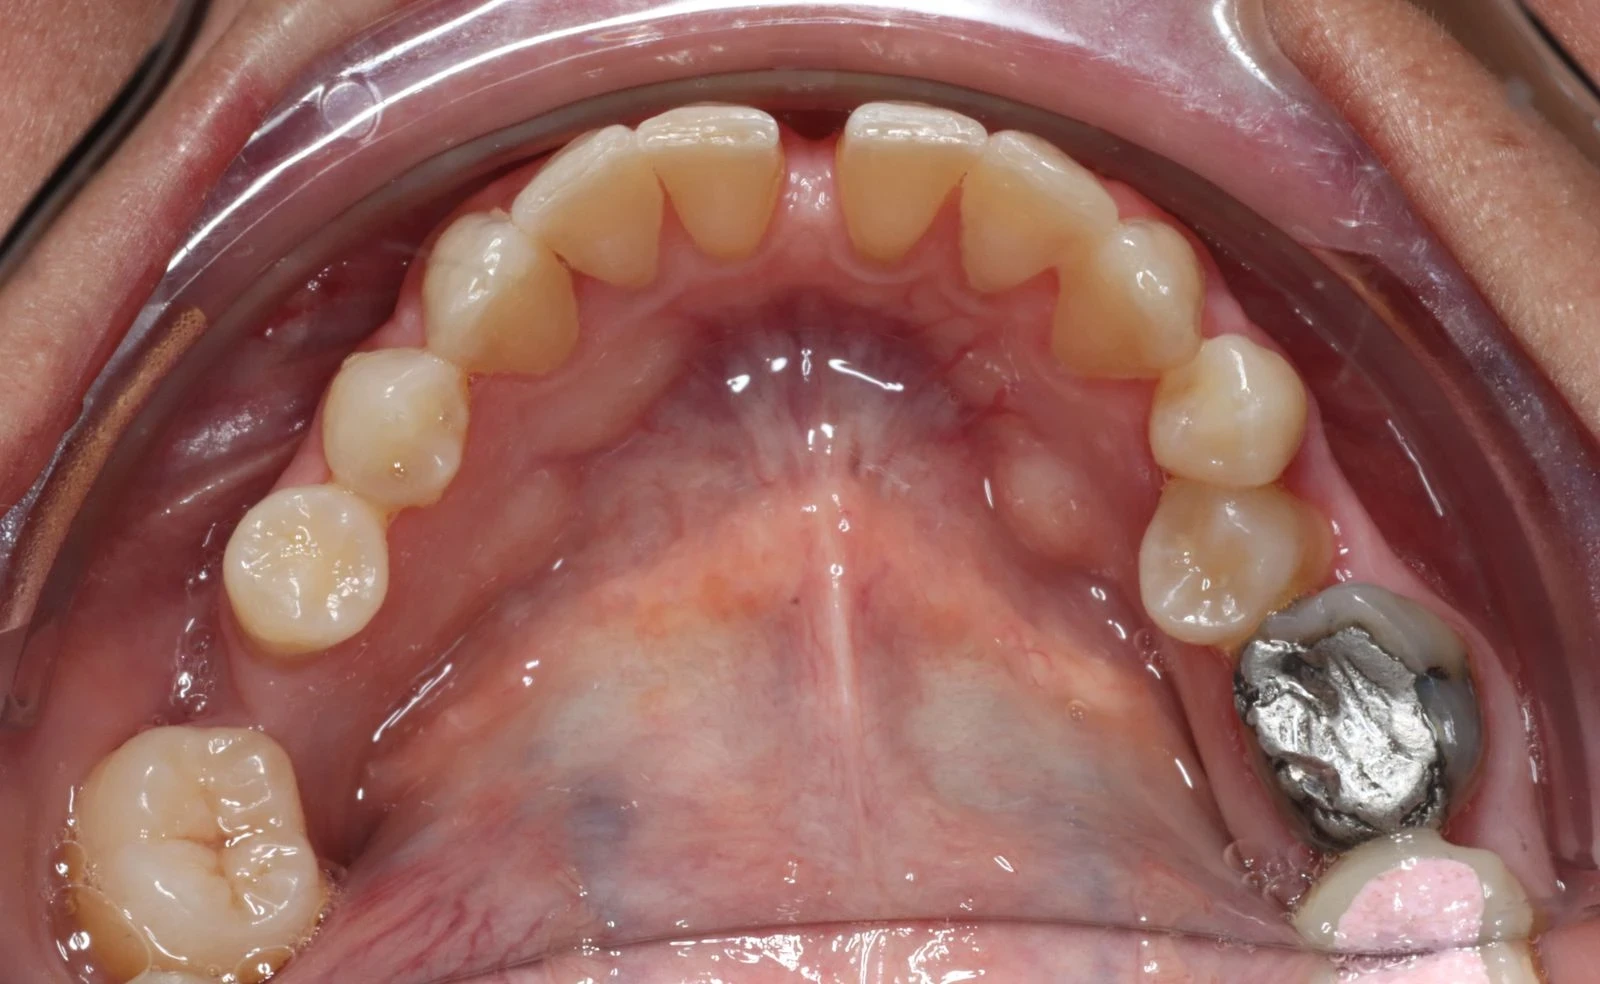

Contentions

Qu'est-ce que la contention dentaire et à quoi sert-elle ?

La période de contention dentaire est tout aussi importante que la période active du traitement d’orthodontie.

À la fin d'un traitement, il est nécessaire de consolider les résultats obtenus afin d’éviter que les dents ne se déplacent à nouveau. En effet, après le port d'un appareil dentaire, qu'il s'agisse de bagues classiques, d'un appareil lingual ou même d'aligneurs transparents, le risque de récidive est important, en raison de multiples facteurs tels que :

On distingue deux types d'appareils de contention :

Les contentions fixées : il s’agit de fils de contentions que l’on colle sur les faces internes des dents.

Les contentions amovibles : il s’agit de gouttières de contention, similaires aux gouttières d’alignement, mais dont la rigidité est différente et qui ne se portent que la nuit.